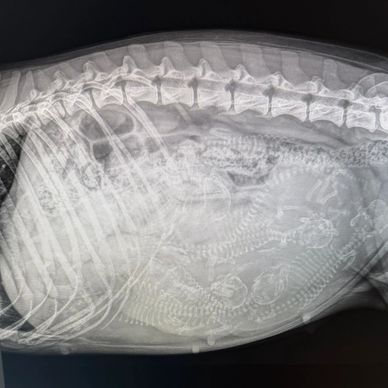

Jinsha hatte heute einen Termin fürs Röntgen. Die Tierärztin war

sehr zufrieden. Wir sind sehr glücklich und sehen gespannt auf die nächsten Tage. Wünscht uns Glück für die Geburt!